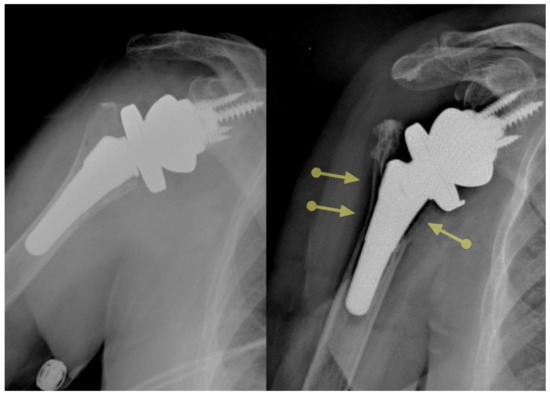

Stems that do not engage the cylindrical portion of the endosteal canal can easily be misaligned. Excessive valgus or varus will lead to a poor humeral head position in anatomic arthroplasty. Similarly, poor alignment can lead to a reverse polyethylene that is excessively horizontal with an increased risk of notching, or to a more vertical polyethylene that may facilitate dislocation. Certain short stems have been designed with just enough length to avoid malalignment [17]. Stemless prostheses are also at risk for malalignment (Figure 1). As such, care must be taken to optimize the humeral head cut to minimize the chances of malalignment with ultrashort stem and stemless prostheses.

Figure 1.

Ultrashort stems (A) and stemless prostheses (B) are at increased risk for malalignment.